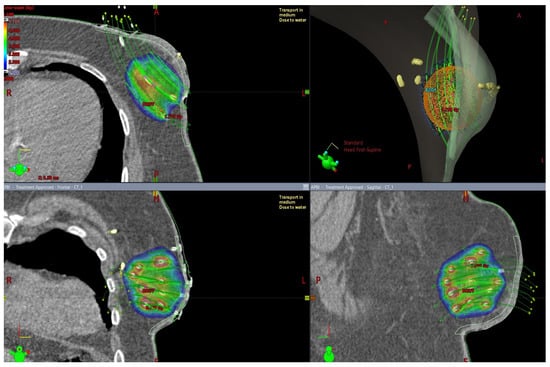

The issue of using radiotherapy in patients who have undergone immediate breast reconstruction and in whom post-mastectomy radiation therapy (PMRT) is indicated remains controversial. Available data indicate that a majority of patients undergoing immediate reconstruction have an implant placed during the surgery [58]. Figure 3 presents an isodose plan for a patient with an inserted silicone implant.

Figure 3.

Breast irradiation after radical mastectomy with silicone implant insertion. A dose greater than 90% of the prescribed dose is displayed in color. The maximum dose in this slice is 105.6 % of the prescribed dose.